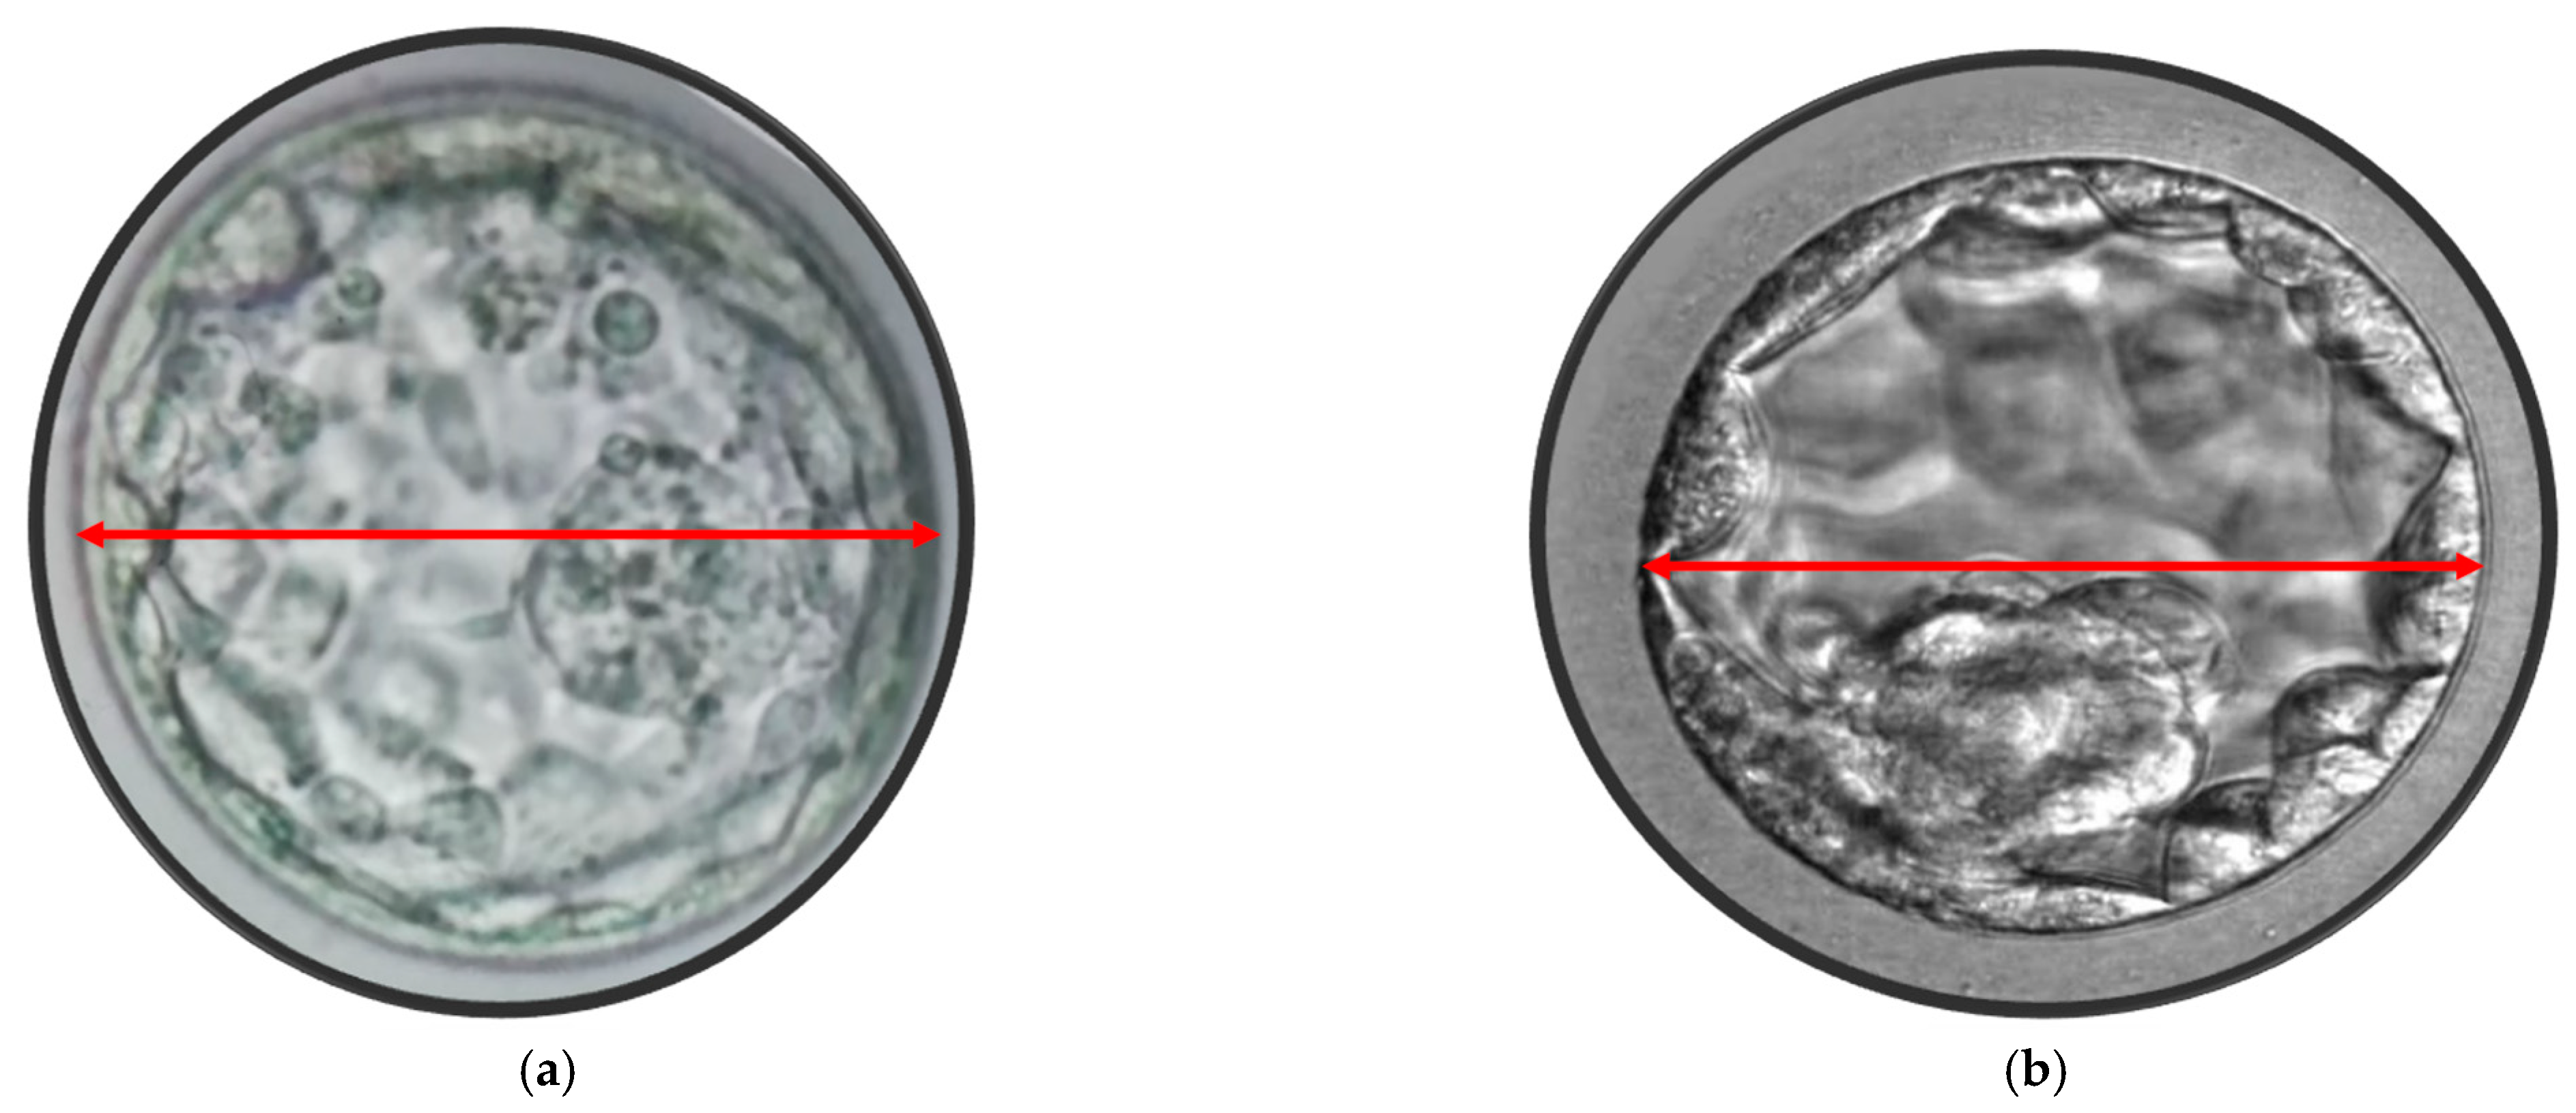

- Sciorio, R.; Thong, D.; Thong, K.J.; Pickering, S.J. Clinical pregnancy is significantly associated with the blastocyst width and area: A time-lapse study. J. Assist. Reprod. Genet. 2021, 38, 847–855. [Google Scholar] [CrossRef] [PubMed]

- Sciorio, R.; Meseguer, M. Focus on time-lapse analysis: Blastocyst collapse and morphometric assessment as new features of embryo viability. Reprod. Biomed. Online 2021, 43, 821–832. [Google Scholar] [CrossRef] [PubMed]

- Lagalla, C.; Barberi, M.; Orlando, G.; Sciajno, R.; Bonu, M.A.; Borini, A. A quantitative approach to blastocyst quality evaluation: Morphometric analysis and related IVF outcomes. J. Assist. Reprod. Genet. 2015, 32, 705–712. [Google Scholar] [CrossRef]

- Utsuno, H.; Ishimaru, T.; Matsumoto, M.; Sasamori, C.; Takahashi, H.; Kimura, H.; Kamijo, S.; Yamada, M.; Tanaka, M.; Hamatani, T. Morphometric assessment of blastocysts: Relationship with the ongoing pregnancy rate. F S Rep. 2022, 4, 85–92. [Google Scholar] [CrossRef] [PubMed]